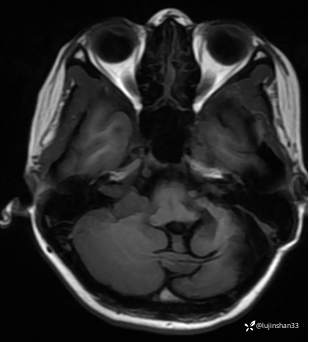

第一次术前颞骨CT及MRI:

第二次术前CT及MRI